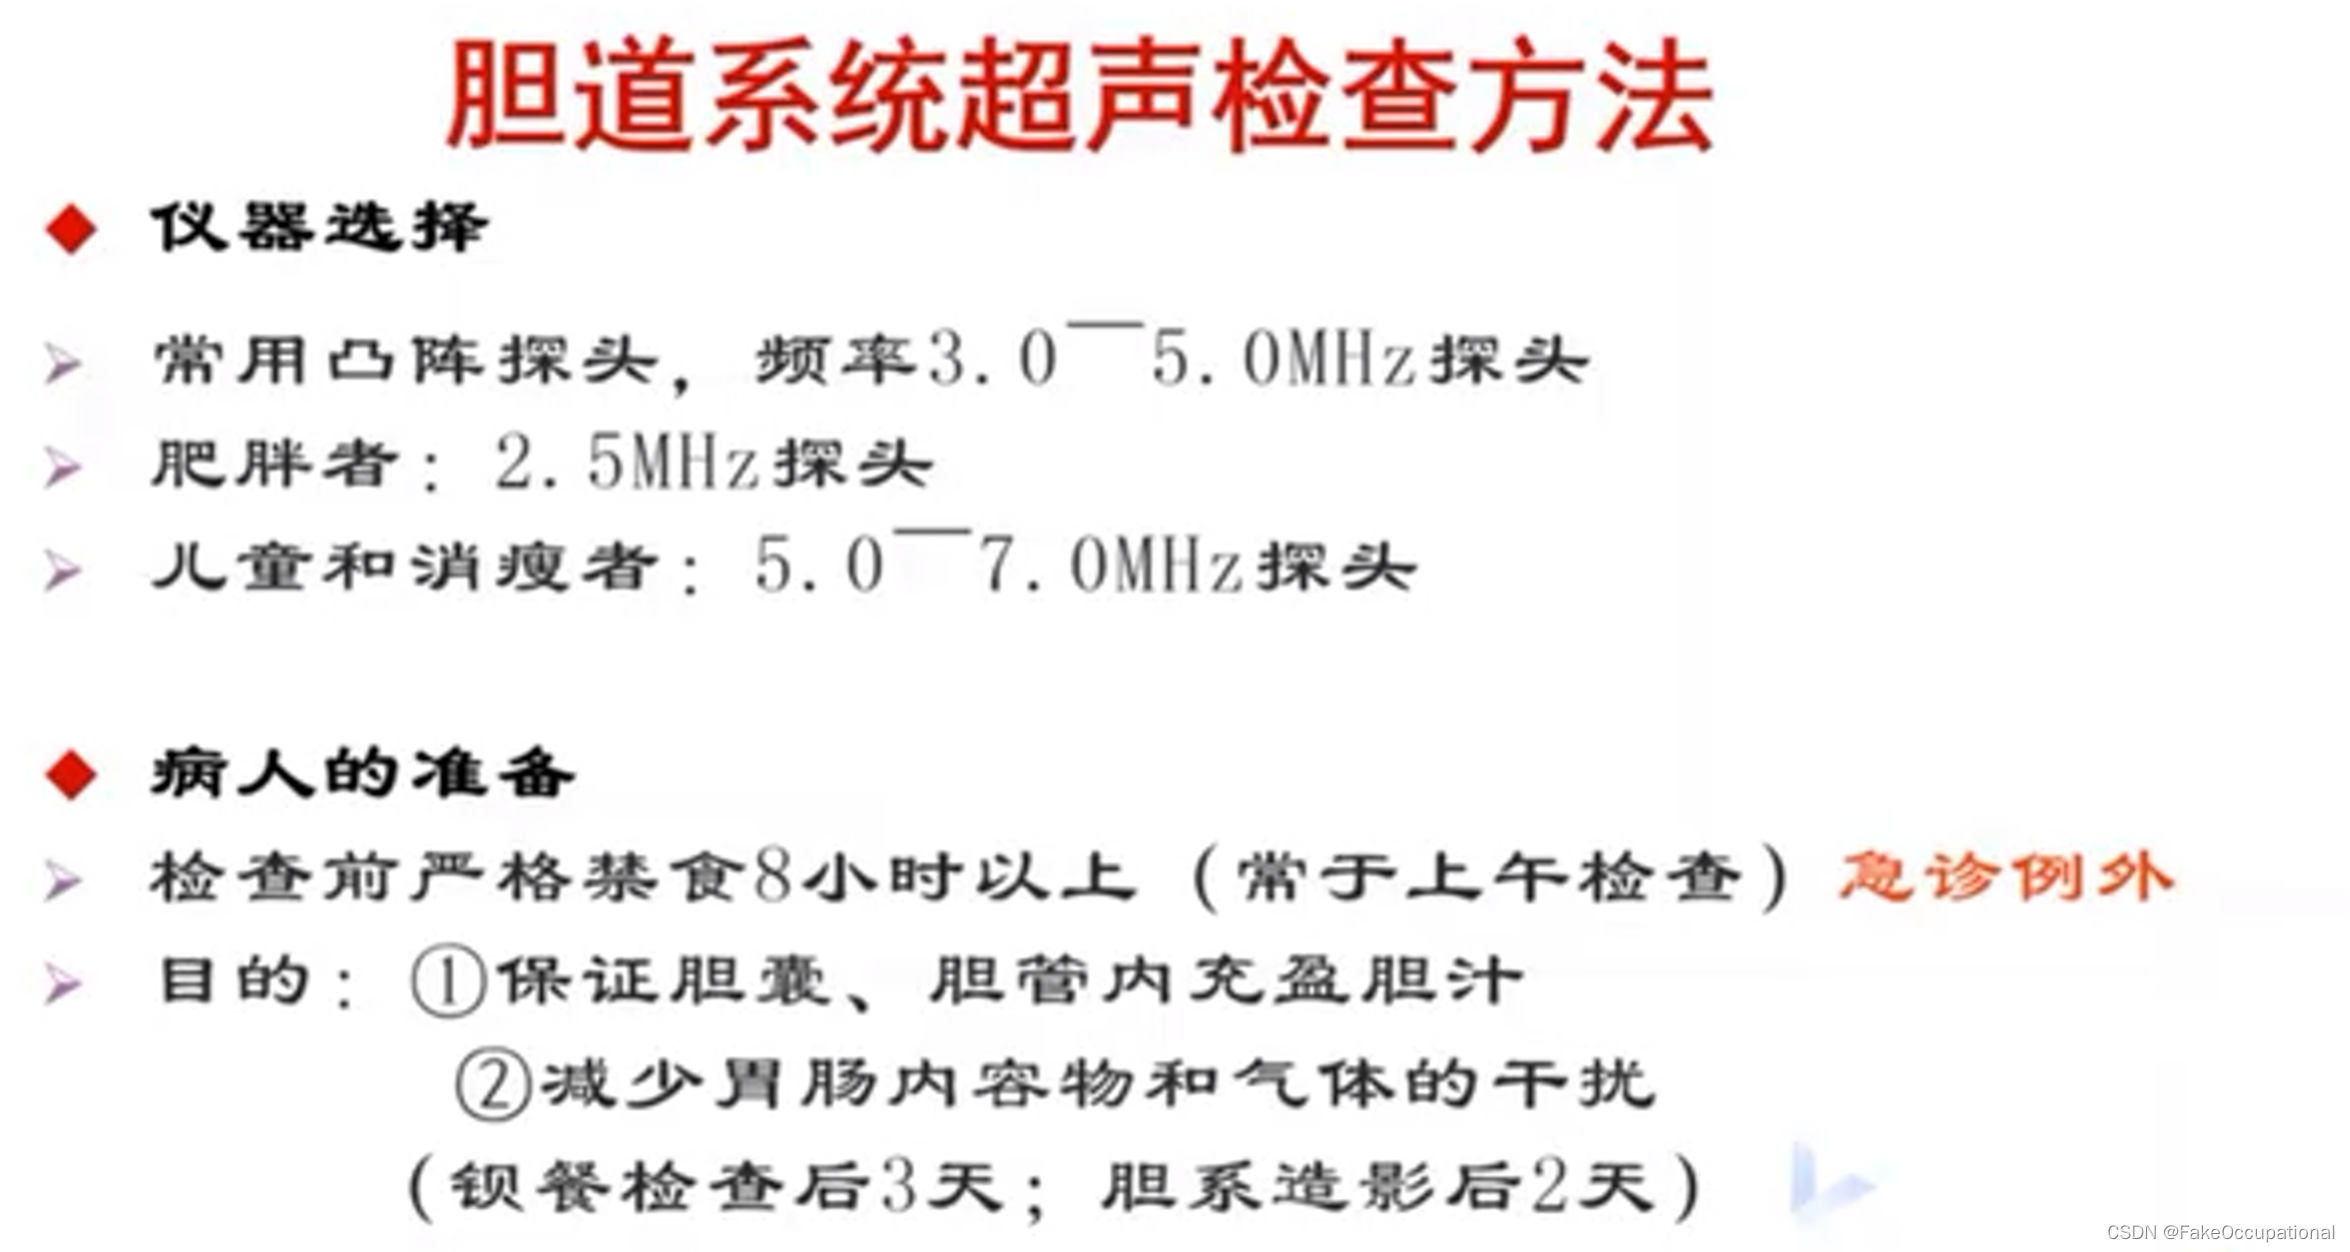

胆道系统检查技术